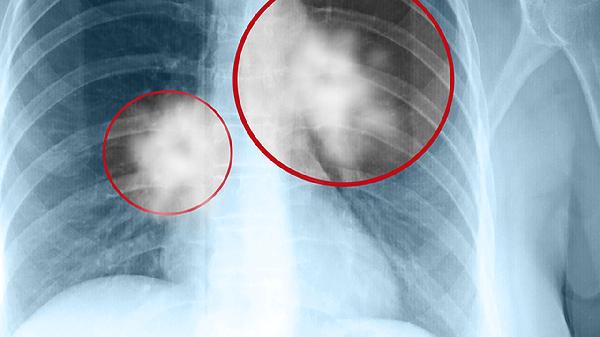

肺功能的健康对于我们的整体健康至关重要。了解肺部的健康状况并不需要复杂的设备或程序,有三种简单的检查方法可以帮助我们初步评估肺功能。这些检查方法包括肺活量测试、呼气流速测量和氧饱和度检测。通过这些简单的步骤,我们可以对自己的肺功能有一个基本的了解,并在必要时采取进一步的措施。

1、肺活量测试:这一测试是评估肺部健康的常用方法之一。通过深吸一口气,然后尽可能快地将气体呼出,我们可以测量出肺活量。肺活量是指一次呼吸能够吸入和呼出的最大气体量。肺活量的大小可以反映出肺部的弹性和气道的通畅程度。通常情况下,肺活量较低可能提示肺部有问题,如哮喘或慢性阻塞性肺病。如果发现肺活量异常,建议及时咨询医生进行进一步检查。